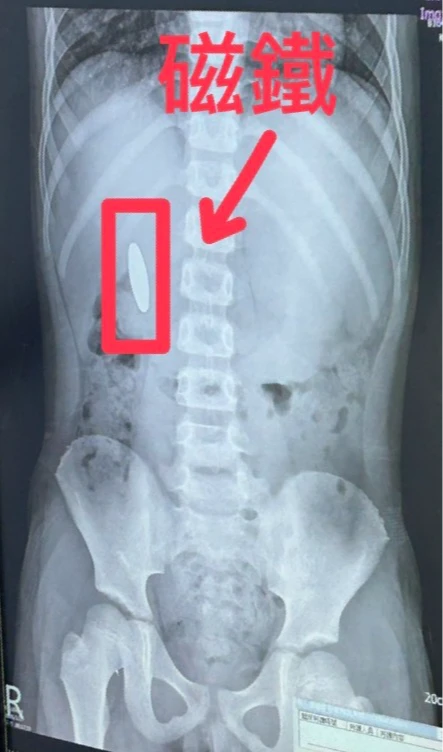

台南市議員林燕祝今揭露台南一名小一生在補習班遭小五生逼吞3公分磁鐵,透露本案1月27日發生,南市教育局證實此事,並指男童已由醫院醫師評估並開立軟便劑,協助異物自然排出體外,但至今天中午為止,磁鐵仍在腸中,尚未自然排出。

若家長懷疑孩子吞下磁鐵,刁茂盟建議,應立即就醫照X光,才能清楚定位是否在食道、胃或腸道,如果確認吞進磁鐵,多半需要住院追蹤,此時不建議催吐,尤其若多顆磁鐵在體內移動,反而可能增加腸道受傷風險。

刁茂盟說,若磁鐵卡在體內未妥善處理,症狀可能隨時間加劇,包括腹痛、嘔吐、腹脹,甚至血便、吐血;最嚴重可進展為腸穿孔與腹膜炎。一般腸道蠕動下,多數異物三天內會移動;若三天仍未移動,照X光發現位置固定,風險會顯著升高,須積極處置。